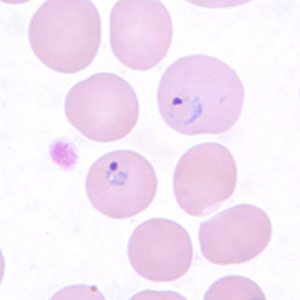

P. vivax

P. ovale

P. malariae

P. falciparium

Babesia